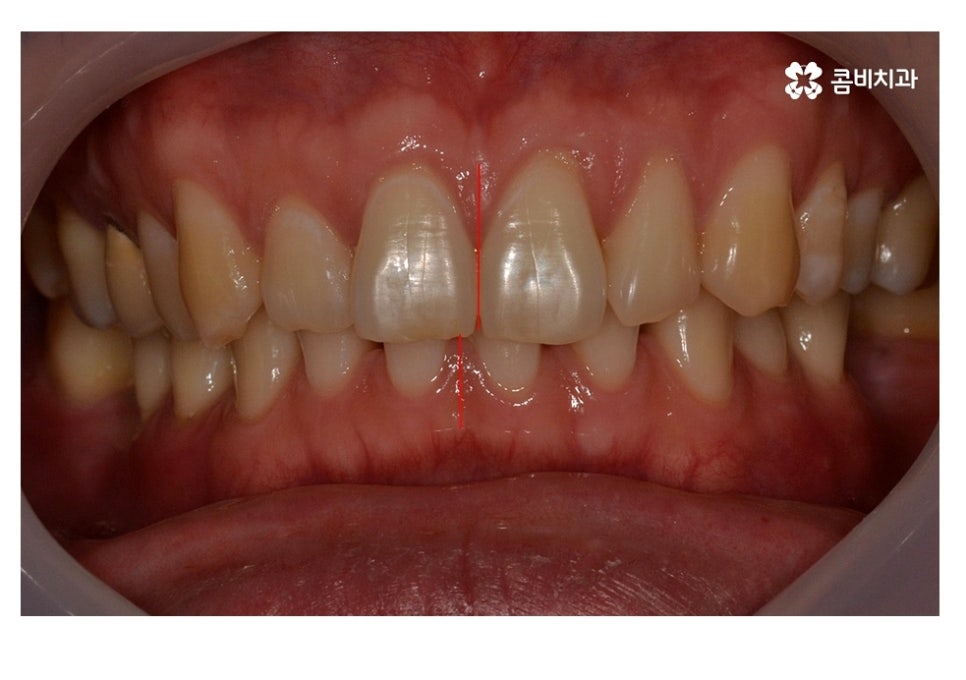

위 사례 이미지에서 보시는 것과 같이 불규칙한 치열 외에도

치아 사이가 벌어져 있으면 심미성 뿐 아니라

음식물이 치아 사이에 끼기 쉽기 때문에 충치, 잇몸질환이

발생하기 쉬울 수 있어요.